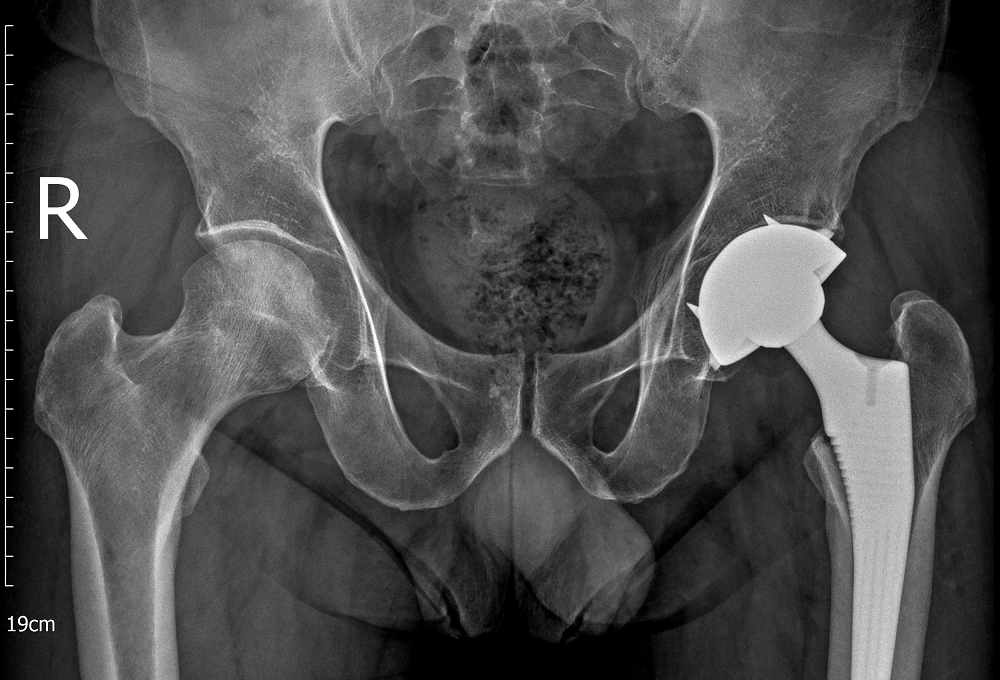

Qua thăm khám lâm sàng kết hợp chẩn đoán hình ảnh như X-quang và MRI, các bác sĩ xác định người bệnh bị hoại tử chỏm xương đùi hai bên, trong đó khớp háng bên trái đã tổn thương nặng hơn. Kết quả chẩn đoán của bác sĩ khiến người bệnh bàng hoàng.

Bệnh nhân được bác sĩ thực hiện thành công cuộc phẫu thuật thay khớp háng toàn phần bên trái

Với trường hợp này, khớp háng trái đã tiến triển đến giai đoạn nặng, không còn khả năng bảo tồn, các bác sĩ buộc phải chỉ định thay khớp háng toàn phần nhằm giảm đau, phục hồi chức năng vận động và tránh nguy cơ tàn phế cho người bệnh. Trong khi đó, khớp háng bên phải vẫn còn khả năng bảo tồn nên các bác sĩ lựa chọn phương pháp phẫu thuật giảm áp cổ xương đùi để cải thiện tuần hoàn, làm chậm quá trình hư khớp.

Ca phẫu thuật thay khớp háng bên trái được thực hiện thành công. Chỉ sau một ngày, người bệnh đã có thể ngồi dậy, co duỗi háng và tập phục hồi chức năng. Sau 48 giờ, ông P. đi lại được mà không cần trợ giúp, mức độ đau giảm rõ rệt. Ba tuần sau, khi khớp háng bên trái đã ổn định, người bệnh tiếp tục được phẫu thuật giảm áp cổ xương đùi bên phải. Nhờ can thiệp đúng thời điểm, khớp háng còn lại được bảo tồn giúp ông P. đi lại bình thường, không còn tình trạng dáng đi khập khiễng.

Sau phẫu thuật, sức khỏe và khả năng vận động của bệnh nhân đã bình phục tốt